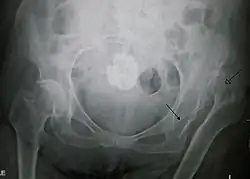

| Congenital dislocation of the left hip in an elderly person. Closed arrow marks the acetabulum, open arrow the femoral head. | |